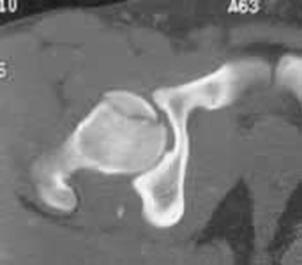

Luxatie de sold stang Luxatie de sold stang

Fractura

de cap femural  Fractura de cap femural

Aspect

CT

de cap femural Fractura subcapitala cu usoara deplasare

Aspect CT